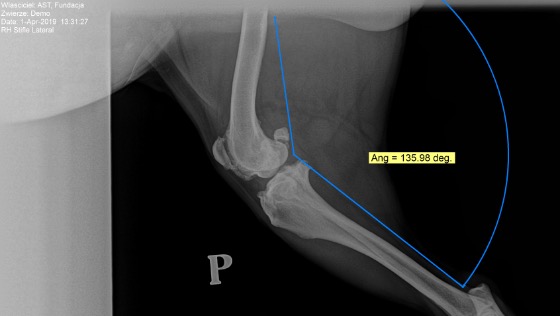

Jutro operacji rekonstrukcji zerwanego więzadła krzyżowego zostanie poddany DEMO. Pies ma rotacje piszczeli w obu łapach + oba zerwane więzadła krzyżowe. Wymaga operacji na oba kolana :( Będzie operowany metodą TPLO - konsultowaną u dwóch ortopedów. Będzie miał wszczepianą dłuższą płytę, stąd wyższy niż przeciętny koszt operacji. Na razie zajmiemy się prawą łapą a po wygojeniu lewą.

Zbieramy 3 tys zł na operację TPLO która jutro jest planowana.

----------------Demo jest już po udanej operacji. Było trudno z uwagi na rotację piszczeli ale z sukcesem.